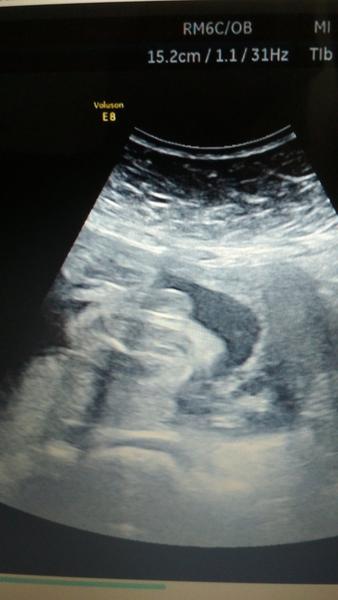

Holky, co vidíte? Kluk nebo holka?

Ahoj holky,jsem uz v 7.mesici a lekari se nemuzou shodnout.Jeden rika 100%holka,druhy zase 100%kluk.Co vidite vy?

@cysticka no je to foto rozkroku,nevim zda tam jsou steheni kosti a kostrc a na druhe strane pipinka.Uz mam doma 2 kluky a ty to meli jine 😂

No u prvnich dvou kluku to bylo jasne take kolem 5 mes.i jsme to na UZV poznali,ale tohle je jine.2x se nam už gynekolog trefil a ted kdyz rekl ze je to holka,tak jsme byli šťastní,jenze vcera v Praze na 4D nam hned rekli kluk,ani nezavahali,proste podle nich hotovka.